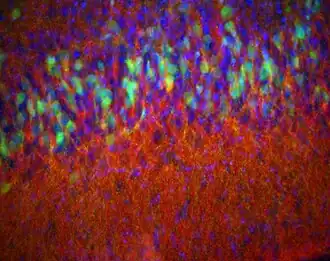

![]() Пириформная кора 14-дневного мышонка, окрашенная иммуногистохимически на энкефалин (красный), D2- и EGFR-рецепторы (зелёный) и белок DAPI (синий) для того, чтобы было видно отдельные ядра (группы клеток) | |